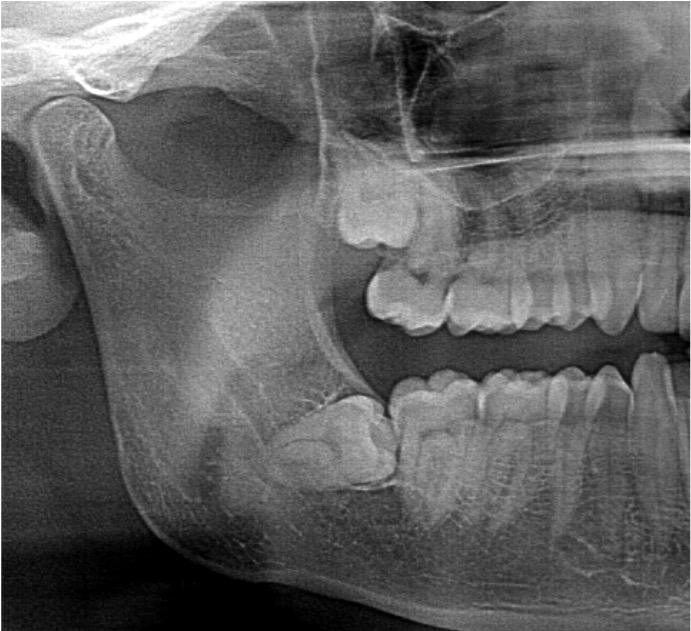

The force that pushes a tooth into the mouth is the formation of the root, which acts like a rocket to propel it, ideally, into the perfect position. The crazy thing is, the longer the roots get, the closer they get to important structures like the sinuses (near top wisdom teeth) and a nerve that gives the feeling to your lower lip and chin (bottom ones). If those roots get super close, touch, or “wrap around” those structures, there is increased risk of damage.

Fortunately injuries to these things are rare, but when they happen, they can be a problem. Here’s what we see on basic x-rays: